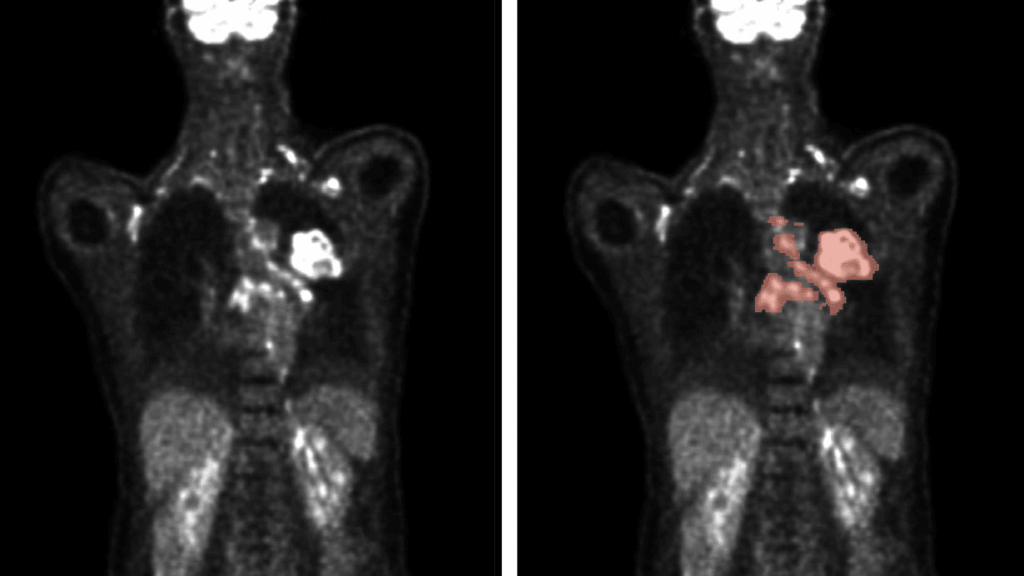

L’analisi delle immagini prodotte dalla tomografia a emissione di positroni (PET) e dalla tomografia computerizzata (CT) è fondamentale nella diagnosi del cancro. La PET utilizza radionuclidi, come il fluorodeossiglucosio marcato con fluoro-18, per evidenziare i processi metabolici del corpo, distinguendo le cellule tumorali maligne da quelle benigne grazie al loro metabolismo accelerato. La CT, invece, permette di visualizzare con precisione l’anatomia del corpo, offrendo una mappatura accurata della localizzazione dei tumori.

Il progetto ha utilizzato un vasto database annotato di immagini PET/CT per addestrare gli algoritmi. I risultati dimostrano che un approccio basato su ensemble di algoritmi, che combina i migliori modelli disponibili, è più efficace rispetto all’utilizzo di singoli algoritmi.

Questo sistema riesce a individuare con precisione le lesioni metaboliche attive, evidenziando come la progettazione dell’algoritmo e le scelte relative al post-processing dei dati siano determinanti per la sua efficacia.